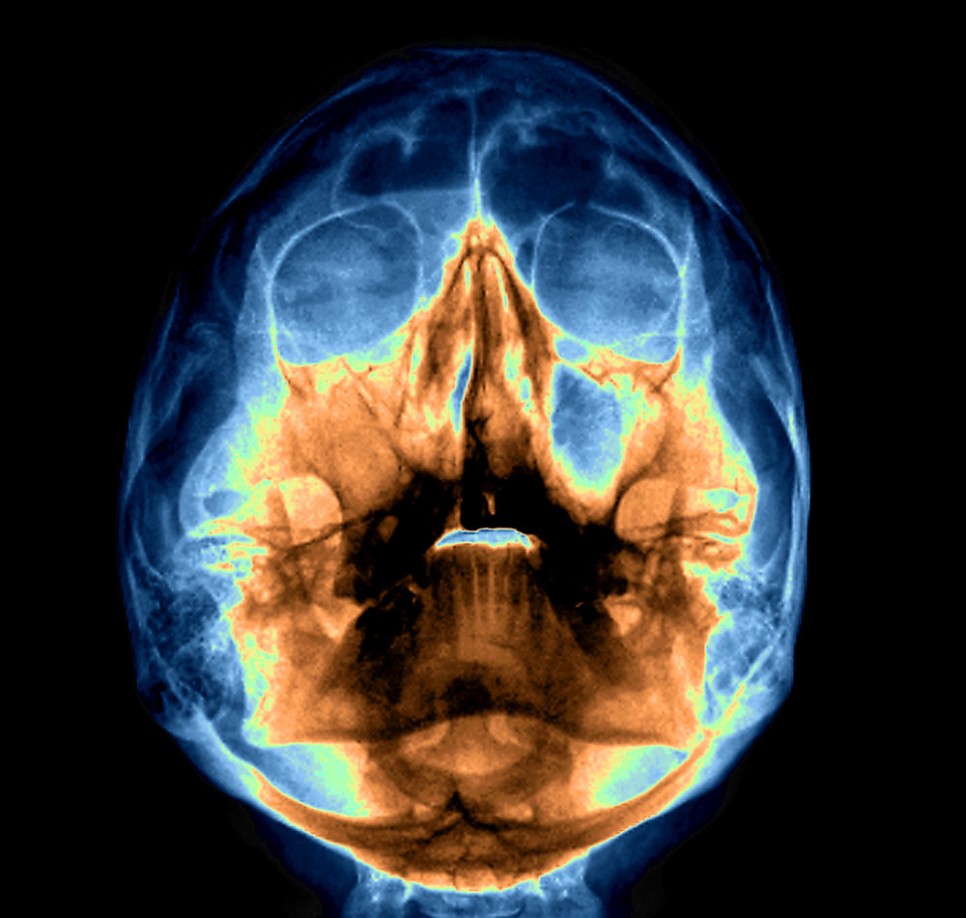

축농증은 부비강염이래요.얼굴 뼈에 있는 8개의 부비동에서 분비물이 배출되지 않고 고름이 나오는 것입니다.

얼굴에 부비강이라는 공간은 평소 공기로 채워지면서 코와 입으로 들어오는 공기가 폐로 들어가기 전에 적절한 온도와 습도를 변환시켜주는 역할을 하는 필터입니다.

또한 뇌와 눈, 코 등 머리의 중요한 부위에 대한 충격을 완화해 주는 역할도 합니다.

따라서 이 부비강 내에 염증이나 고름이 나오면 외부와의 환기가 어려워져 우리 몸에도 악영향을 미칩니다.